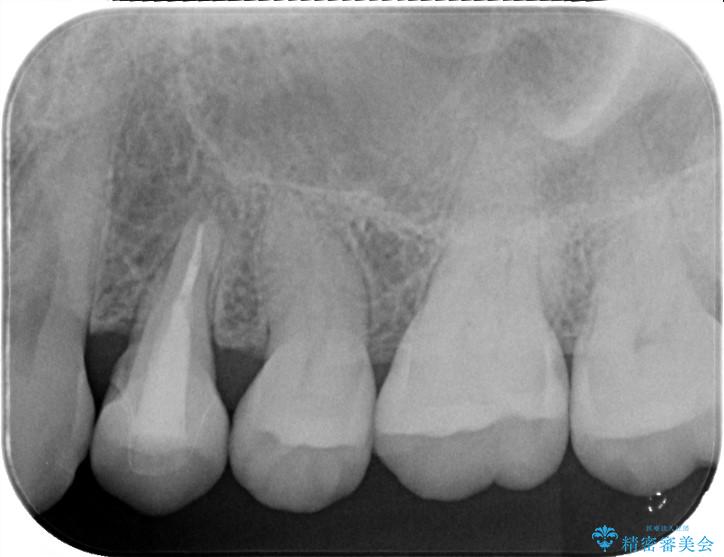

検査の結果、左下4番の歯周ポケットが非常に深くなっていました。これは、歯の根が割れている「歯根破折」の典型的なサインです。

患者様には、根の部分が割れている可能性を説明し、被せ物を外して内部を直接確認することとしました。

根が真っ二つに割れている「垂直性歯根破折」の場合、残念ながら歯を残すことが難しく、放置すると周囲の骨まで溶かしてしまいます。そのため、抜歯後の噛み合わせを回復する方法として、隣の歯を削らずに独立して噛めるインプラント治療をご提案しました。

被せ物を除去し、マイクロスコープにて内部を強拡大で確認したところ、歯の根の深い位置まで真っ直ぐにひびが入っていることを確認し、保存が不可能な状態であったため抜歯をすることとなりました。